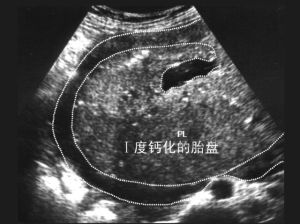

胎盤鈣化鈣化程度1~3度

依據胎盤鈣化斑點分布的大小與狀況,我們可將鈣化區分為3度。第1度指輕微,而第3度指嚴重。

超音波可約略看出,一般以超音波檢查鈣化的情況不見得準確,若要確認,須根據胎盤娩出後實際檢視胎盤鈣化狀況面積來決定。影響

胎盤血流降低。胎盤鈣化所引發的不良影響是胎盤血流降低,導致胎盤功能減退。正常情況下,懷孕後期甚至過期,超音波檢查均或多或少會發現胎盤有1~2度的鈣化,這是這一時期不可避免的現象,也是胎兒已近足月或過期的間接表征。處理原則

胎盤鈣化一旦發生,應該儘早發現儘早治療,不要害怕慌張。胎盤鈣化常發生於妊娠第3期之後,最常見於懷孕過期的胎盤。正常情況下,懷孕後期甚至過期,超音波檢查均或多或少會發現胎盤有1~2度的鈣化,是這時期不可避免的現象,也是胎兒已近足月或過期的間接表征。胎盤鈣化不見得會造成胎盤功能的喪失,危及胎兒。一旦發生第3度嚴重鈣化且合併有羊水過少或其它異常病徵時,可能代表胎盤功能不全,可能危害胎兒,此時則須考慮催生引產、終止妊娠。預防保健